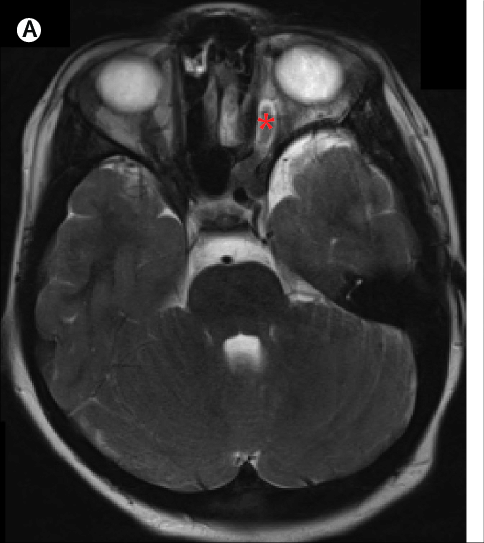

去到医院后做进一步检查发现,怡怡的颅内肿瘤长在两侧视神经交叉的部位上,这种肿瘤学名叫【视神经胶质瘤】,这是一种良性肿瘤,如果能全切就能达到治愈的目的,但是全切谈何容易。

如果全切势必会伤到视神经,孩子的视力就没了;如果不切,其他治疗办法效果不佳,不但视力会越来越差,而且肿瘤要是继续进展的话孩子命都没了。所以手术的难点就是把握一个“度”,一个既能最大限度切了大部分肿瘤,又能保住视力的“度”,这个手术有50%会失败,有50%会成功。

医生把一切风险都告知怡怡父母,让他们决定是否要做这个手术,深思熟虑后,他们决定相信医生赌一把。最后,手术成功了,怡怡颅内的肿瘤近全切,而且左眼视力由0.4提升到0.6,右眼视力由40cm到1m,怡怡顺利出院了。